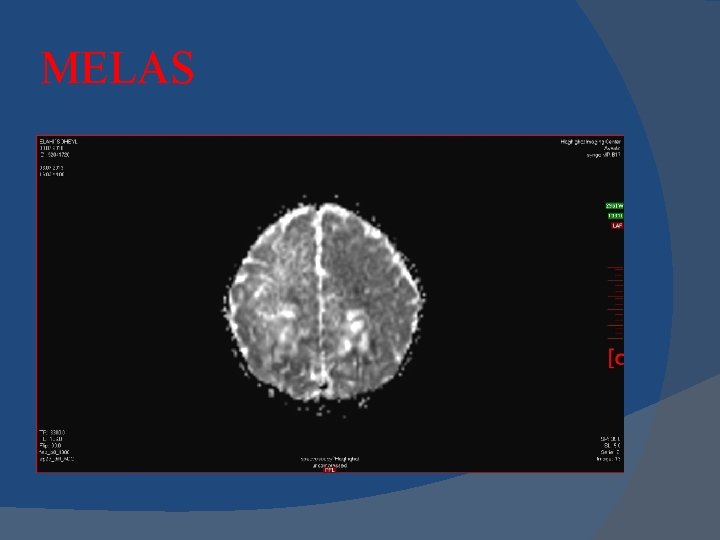

MELAS Mitochondrial myopathy, encephalopathy, lactic acidosis, and stroke-like episodes (MELAS)

MELAS Imaging Stroke-like cortical lesions crossing vascular territories , Posterior location most common "Shifting spread" (appearance, disappearance, reappearance elsewhere) is classic Lactate (Lac) "doublet" at 1. 3 ppm in 60 -65% MRS Basal ganglia (BG) lesions and calcifications

MELAS is a mitochondrial neuronopathy and involves the entire brain. Therefore, DWMR spectroscopy can find some useful intracellular pathophysiologic information that conventional MR imaging cannot display. In conclusion, it is a very useful noninvasive technique for brain diseases apart from cerebral infarction.